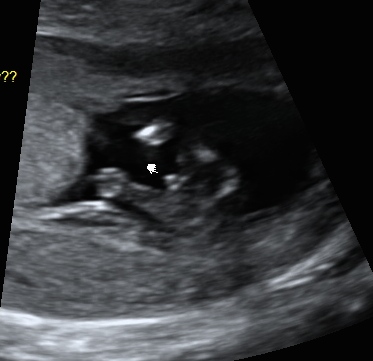

Boy!! It actually looks very similar to our nub shot! Have a look at my posts please xx